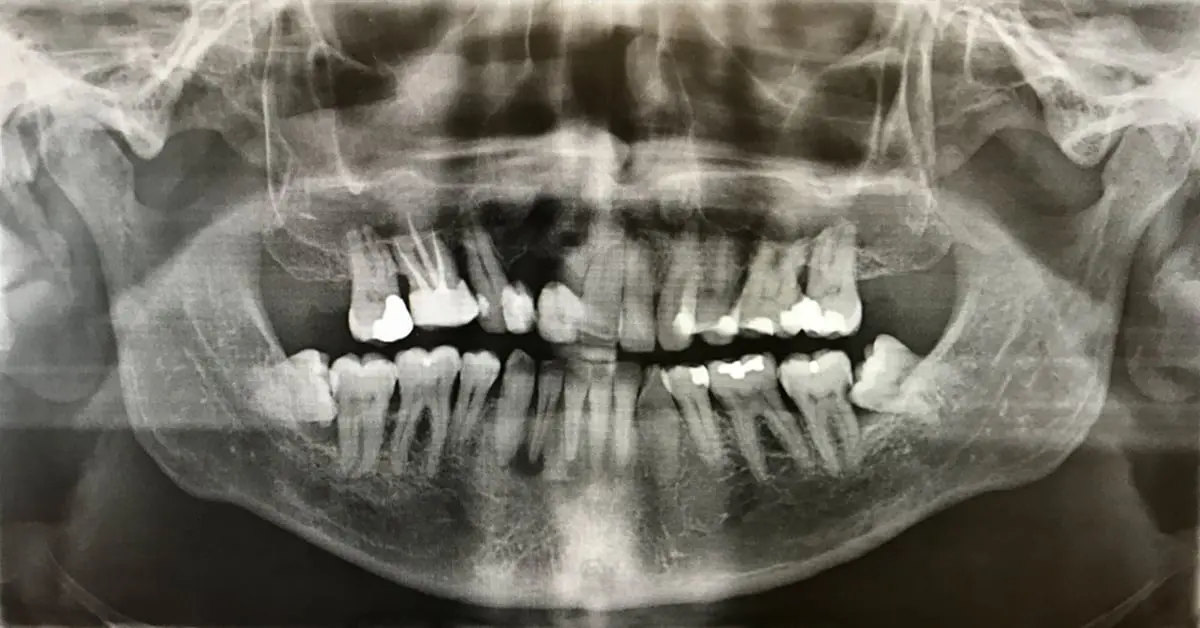

Un dentista hace crecer los dientes en 9 semanas para no tener que usar más implantes dentales